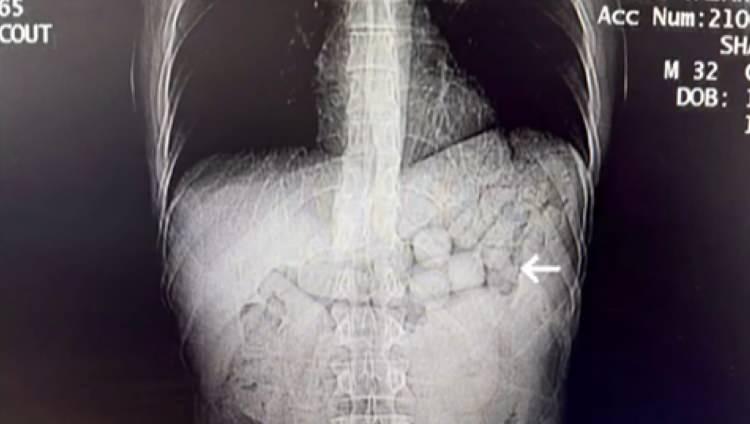

Diyarbakır'da polisin takibe aldığı İran uyruklu iki şüphelinin hastanedeki kontrollerinde, mide ve bağırsaklarında 807 gram uyuşturucu taşıdıkları belirlendi.

Diyarbakır'da otogarda gözaltına alınan ve götürüldükleri hastanede mide ve bağırsaklarında 91 kapsül halinde 807,15 gram metamfetamin çıkan İran uyruklu 2 şüpheli, tutuklandı.